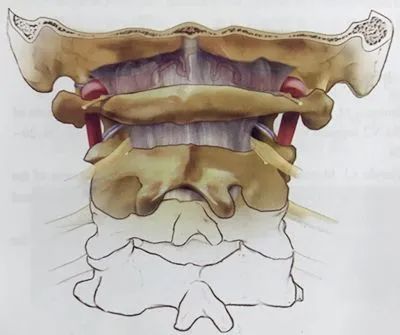

寰椎右份缺如,与颈2、3椎体融合,颈4-6椎融合。

右椎动脉粗大,于颅颈部呈窗型(分3只血管后融合,其中一血管走行寰枢椎连接部间)

1、本例患儿斜颈,是由于C1发育不全、右侧侧块及后弓缺如所致。

2、难点是作为主要供血的右侧椎动脉发育异常,为窗口型分叉,环绕C2椎弓根。